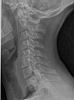

Thorax – Abdomen – Schedel – CWZ – DWZ – LWZ – Bekken – Full Spine – Schouder – Bovenarm – Elleboog – Onderarm – Pols – Hand – Heup – Bovenbeen – Knie – Onderbeen – Enkel – Voet – Full Leg – Transit – Colonografie – E.R.C.P. – I.V.P. – Cystografie – Hysterografie